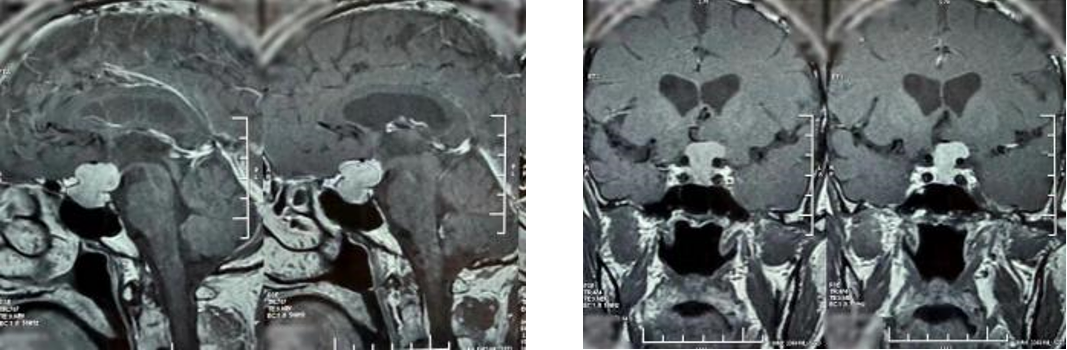

68岁的邓大叔是一位饱受垂体瘤困扰的“老战士”,11年前他经鼻行垂体瘤手术,几年后垂体瘤复发再次通过伽马刀治疗,经过两次历练后的他以为之后就可以高枕无忧,没想到近期的复查报告显示肿瘤“卷土重来”,且这次情况远比之前“棘手”,复发的肿瘤不仅从鞍内生长到鞍上,还与大脑的“生命线”——前交通动脉以及掌管意识记忆的三脑室底粘连紧密,甚至朝一侧颈内动脉上方生长,就像一颗埋在大脑深处的“不定时炸弹”,位置险要,结构复杂。

最终,由张治国医生主刀,为邓大叔顺利实施了这例高难度的经鼻蝶微创手术,肿瘤被完整、精准地切除,紧密粘连的前交通动脉及三脑室底均保护完好。